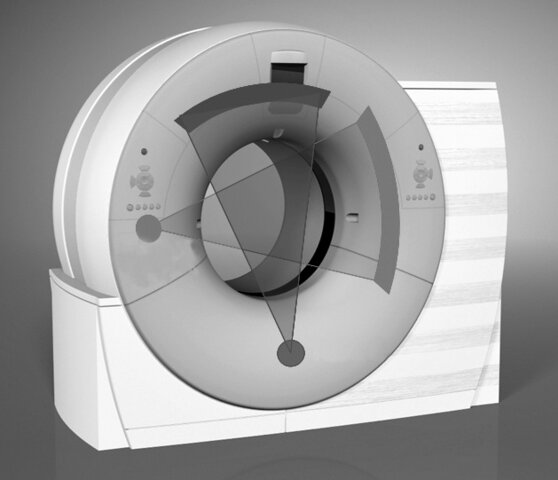

• Hounsfield completa el desarrollo del primer sistema de imagen tomografía computarizada.

Hounsfield completa el desarrollo del primer sistema de imagen tomografía computarizada.

La primera máquina de tomografía computarizada fue creada por Godfrey Hounsfield en Inglaterra. Era un ingeniero que trabajaba en una compañía británica.

• Se presenta la TC de doble fuente (Siemens)

Se presenta la TC de doble fuente (Siemens)

La TC de doble fuente son equipos que tienen dos tubos, esto hace que las imágenes y/o resultados sean de alta calidad y fáciles de obtener.

• Se presenta la TC Helicoidal de 320 cortes (Toshiba)

Se presenta la TC Helicoidal de 320 cortes (Toshiba)

Es un sistema de diagnóstico por imágenes. Fue presentado a la American Society of Radiology Technologist y posee trecientos veinte filas de detectores.